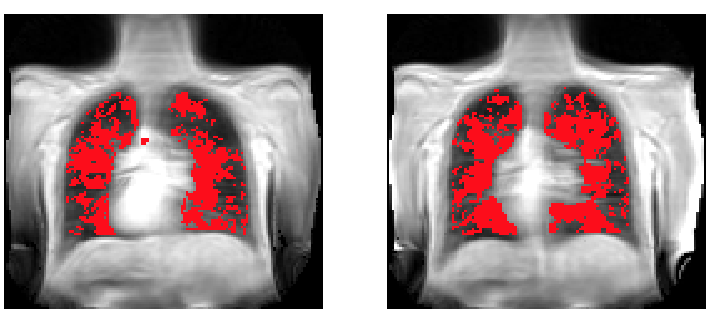

From study design to final reporting, Bioxydyn delivers repeatable MRI biomarkers that reveal tissue function, physiology and change. Our operational excellence and metrology help you compare results across sites, scanners and timepoints.

Disease areas and services supporting quantitative MRI biomarkers across clinical trials.